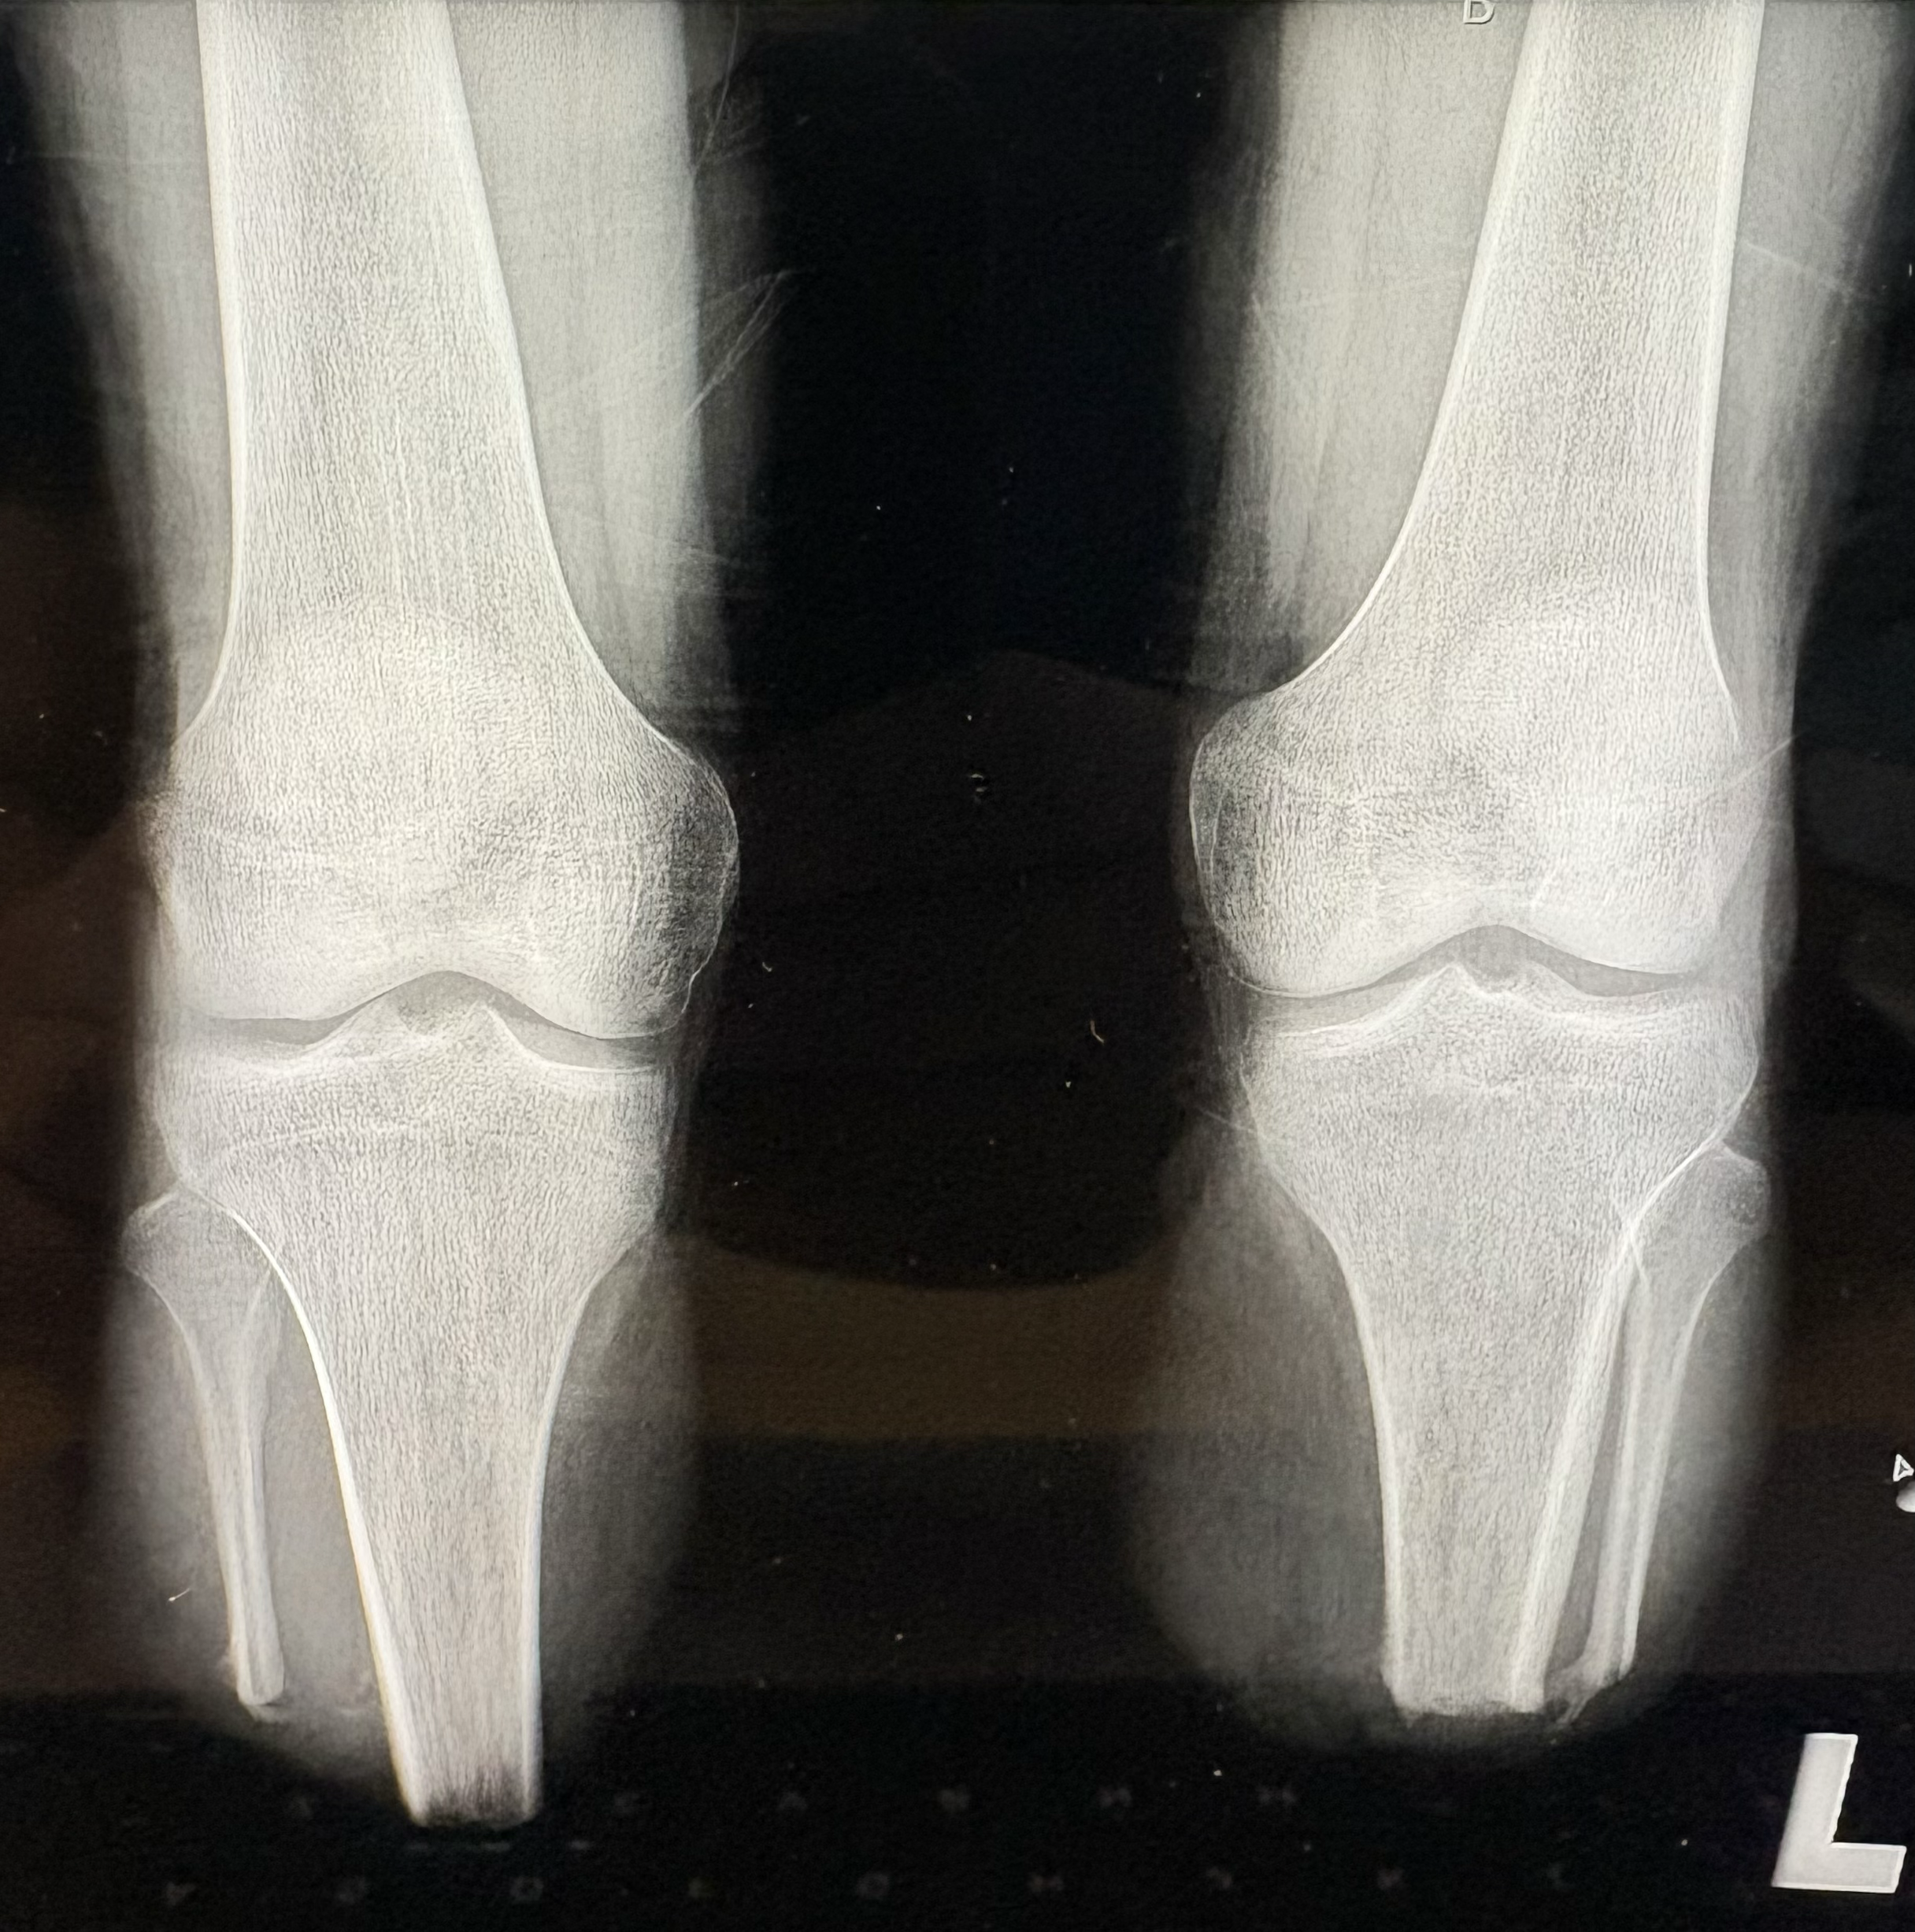

W Klinice Traumatologii i Ortopedii WIM-PIB przeprowadzono innowacyjny i rzadko wykonywany zabieg jednoczasowej osseointegracji obu podudzi u 19-letniego pacjenta po amputacji urazowej. To ważny krok naprzód w nowoczesnym leczeniu osób po amputacjach kończyn dolnych.

Osseointegracja polega na trwałym połączeniu implantu z kością, co umożliwia bezpośrednie mocowanie protezy bez konieczności stosowania tradycyjnego leja protezowego. Rozwiązanie to zapewnia pacjentom większy komfort użytkowania, lepszą kontrolę ruchu oraz wyraźną poprawę jakości życia. Przeprowadzona operacja była szczególnie wymagająca, ponieważ objęła obie kończyny jednocześnie. Jednoczasowe wykonanie zabiegu niesie jednak istotne korzyści – pozwala uniknąć drugiej hospitalizacji i kolejnego znieczulenia ogólnego, skraca całkowity czas leczenia oraz umożliwia prowadzenie symetrycznej rehabilitacji obu kończyn już od początku procesu usprawniania. Dzięki temu pacjent ma szansę szybciej powrócić do samodzielnego funkcjonowania.